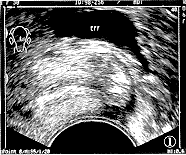

摘要 目的 :探讨经阴道超声早期诊断异位妊娠的声像图表现。方法 :对拟诊异位妊娠的 58例患者及早进行多方位、多切面的经阴道超声检查诊断,并与术后病理诊断相对照。结果 54例为输卵管妊娠, 2例为卵巢妊娠,残角与子宫颈妊娠各 1例。误诊、漏诊共 5例。结论 :应用经阴道超声法诊断异位妊娠,能清楚地显示出微细声像结构特征,从而提高早期诊断异位妊娠的准确性。